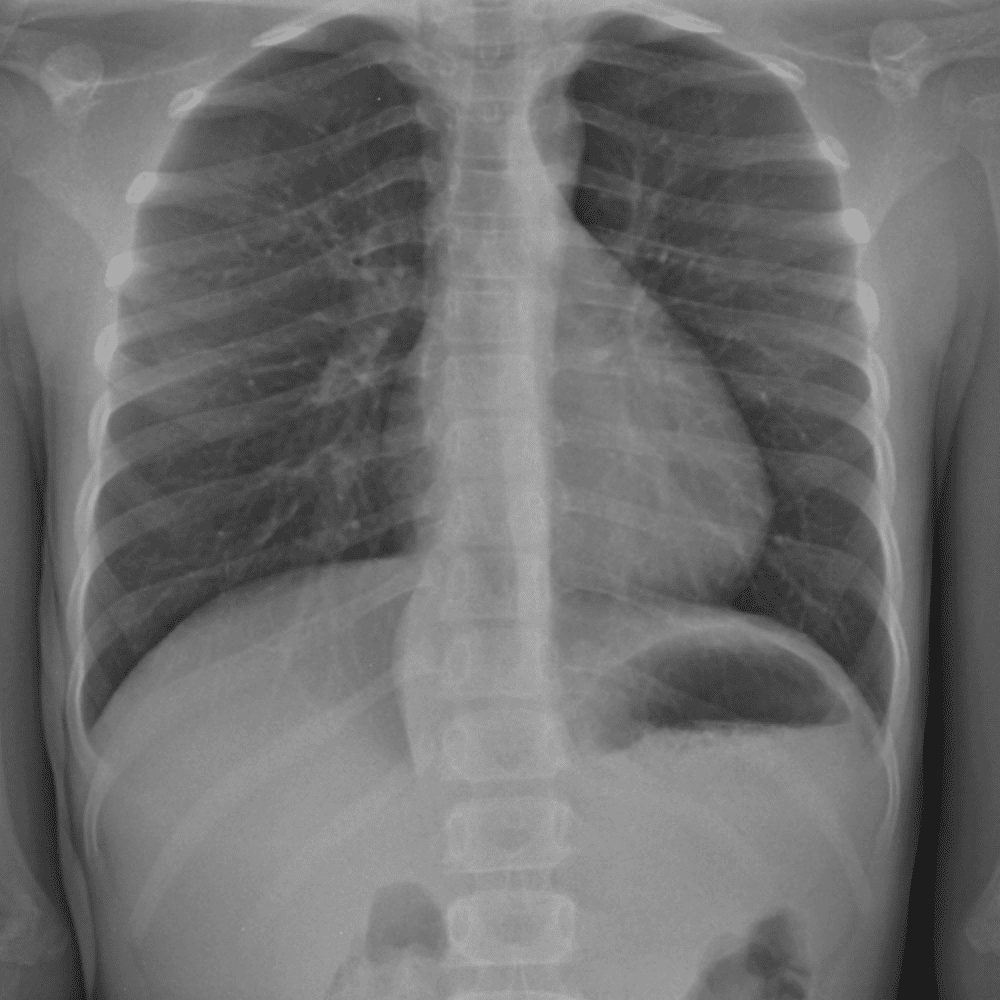

Peds Chest

Practice

Simulates call by including subtle or difficult cases and some normals.

50 cases